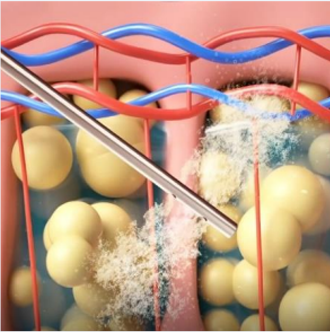

입안을 절개하여 외부 흉터 없이

심부볼 지방을 안전하게 제거합니다.

STEP 02 절개

입안 점막을

STEP 03 지방 제거

심부볼 지방 덩어리를

STEP 04 봉합 및 완성

녹는 실로 꼼꼼히 봉합하여